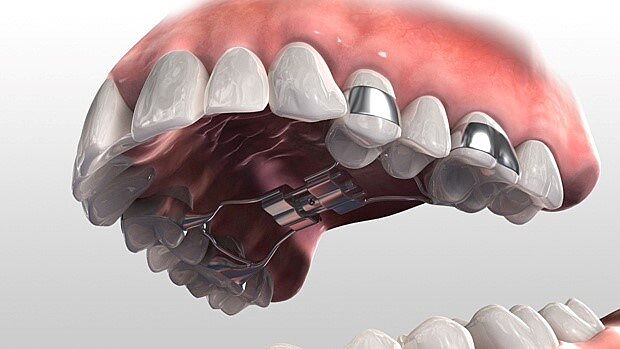

Ортодонт апарат Hybrid Hyrax для розширення щелепи

Пройшло півроку, зробили КТ і ортодонт каже ставити туди само систему-апарат hybrid hyrax.

Це типу мікроімплант на 6 міс також. Верхня щелепа на 10 мм вужча на нижню. Ціна питання 1000 євро... я в шоці якщо чесно. І з 12 років брекети в перспективі також треба будуть.